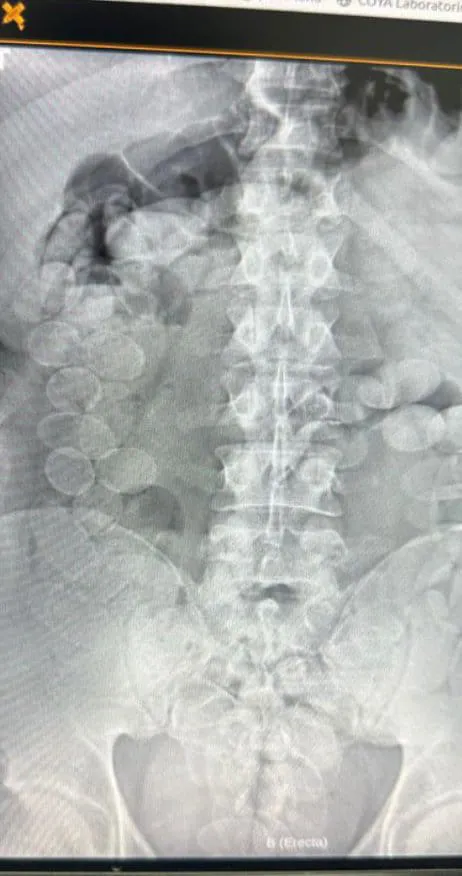

Allí se les realizaron estudios radiográficos, que confirmaron la presencia de múltiples cápsulas en el interior de sus cuerpos. Bajo supervisión médica, los hombres expulsaron 185 cápsulas, que fueron analizadas por personal de Criminalística y Estudios Forenses. El narcotest dio resultado positivo para cocaína, con un peso total de 2 kilos 451 gramos.